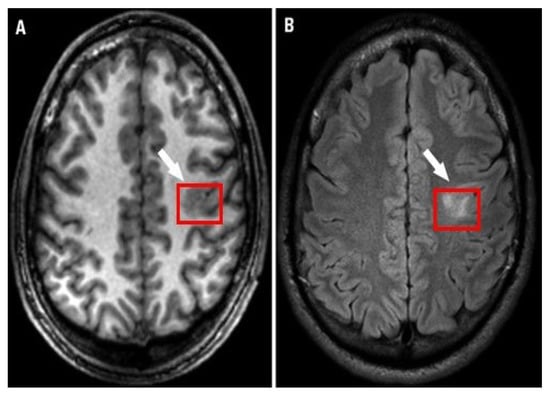

Epilepsy is a neurological disorder. It is characterized by abnormal brain activity. Epileptic patients suffer from unpredictable seizures which cause changes in their behaviour, movement, feelings, and sometimes causes a loss of awareness. The World Health Organization (WHO) estimates that epilepsy affects over 50 million people globally; this large number makes epilepsy the most common neurological disorder. Around three-quarters of epilepsy patients in low- and middle-income countries do not receive the treatment they require, and they and their families face stigma and discrimination in many parts of the world, as per the WHO’s report. Approximately 30% of those patients suffer from refractory seizures [1]. Seizures are considered refractory or drug-resistant when treatment does not succeed in achieving seizure freedom for at least 12 months for any reason [2] or if the treatment fails two or more medicines and a seizure occurs once or more per month over 18 months [3]. During the presurgical workup of drug-resistant epilepsy, specialists seek to determine focal epileptogenic brain lesions to apply resection for those lesions which are predicted to cure epilepsy after resection. Focal cortical dysplasia (FCD) is an epileptogenic lesion that requires surgical intervention for treatment of epilepsy. It is a type of cortical development malformation distinguished by disturbed cortical lamination, balloon cells, dysmorphic neurons, and/or ectopic neurons in the white matter [4,5,6]. FCD type I to FCD type III encompasses a wide range of histological and clinical features [4]; although certain FCDs are easily detectable with traditional neuroimaging, others are more subtle [7]. Neuroradiologists have reported detection rates of FCD type II lesions ranging from 65 to 91 percent [8,9]. Figure 1 shows an example of an FCD lesion. Mesial temporal sclerosis (MTS) is another typical epileptogenic lesion in drug-resistant epilepsy that requires surgical intervention. Figure 2 shows an MTS lesion.

Figure 1.

Focal cortical dysplasia lesion (A) T1-weighted MRI and (B) FLAIR MRI [10].